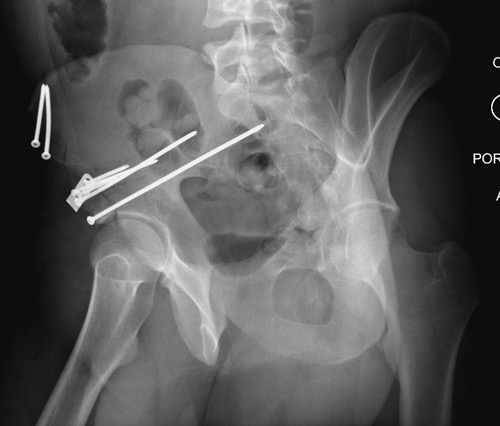

Появились новые проекции. Да, это высокий перелом передней колонны левой вертлужной впадины со смещением.

Относительно диагноза соглашусь с коллегами повреждение крыла и передней колоны вертлужной впадины ближе к типу В по классификации Летурнеля, хотя не в полной мере ей соответствует. Согласно Матта смещение более 3х мм -показание к открытому остеосинтезу, в данном случае скорее из илиоингвинального доступа или Стоппа. Хотелось бы конечно увидеть остальные срезы и рентгенограммы.

Данная картина показывает очень редкий перелом передней колонны, но перед операцией еще раз надо просмотреть обещанные дополнительные КТ срезы.

Представленные слайды Александром из Севастополя, имеет ценность, но, кроме inlet, остальные стандартные Judet рентген снимки должны показать правоту принятого решения. Возможно, здесь фиксация перелома вертлужной впадины, но по рентгену трудно понять!

Здесь пример перелома передней стенки, где сохранен принцип фиксации передней колонны. Для доступа Smith Petersen с остеотомией ASIS. Мышца сарториус отодвинута, и сделана ре-фиксация на свое место винтами. При хорошем обзоре, наличие Farabeuf или Jungblud forceps облегчит репозицию.